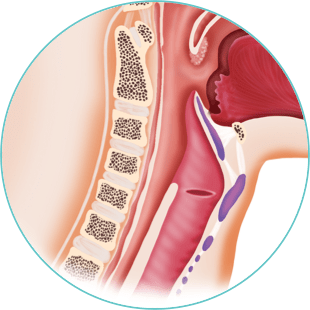

Throat

Lorem ipsum dolor sit amet, consectetur adipiscing elit. Etiam nec aliquam ex, eget consequat est.

- Morbi venenatis non lectus sit amet tincidunt

- Gellentesque sit amet eleifend velit

- Vestibulum fermentum cursus facilisis

- Etiam nec aliquam ex, eget consequat est.

Lorem ipsum dolor sit amet, consectetur adipiscing elit. Ut quis libero eros. Vestibulum fermentum cursus facilisis. Pellentesque sit amet eleifend velit. Donec consectetur posuere tortor a finibus.